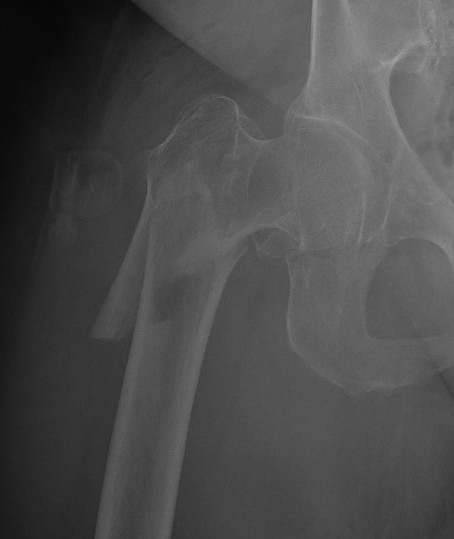

Stability

Depends on medial cortical reduction

Unstable (AO 31.A2 + 31.A3)

- intact lateral wall

- posteromedial cortical fracture

- reverse oblique

- subtrochanteric extension